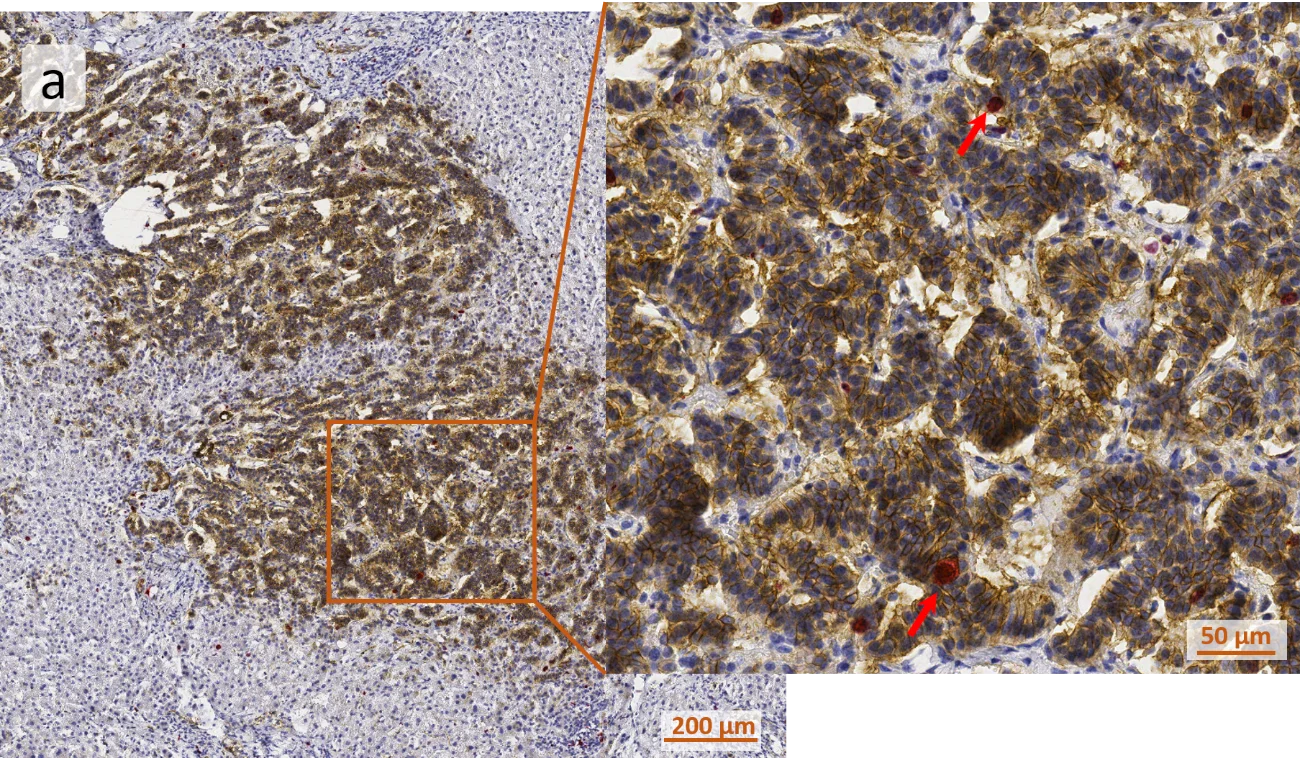

(a) Overview picture of a kidney sample stained for hematoxylin (blue), Ki67 (red), and NCAM (brown). Red arrows indicate Ki67+ cells.

The first step of the analysis was the generation of grey images for the markers, utilized automatically by TG´s color separation algorithm, based on the marker color and intensity: (b) shows the original image, (c) is the nuclei grey image, (d) and (e) represent unmixed gray channels for Ki67 and NCAM correspondingly.